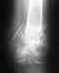

Здравствуйте, ГосподаО себе: 38 лет, пол женский, ранее травм не было, сопутствующие заболевания анемия, варикоз. общее состояние - климакс после оперативного вмешательства, рост 173см, вес 53кг (до травмы) в связи с похудением ноги, наверно вес уменьшился....О травме:09 дек. 2009 в обществ. транспорте падающий пассажир ударил меня головой в ногу чуть ниже колена справа и немного сзади. Я в момент удара удержалась на ногах, но встать на ушибленную ногу уже не смогла.В б-це на основании осмотра и рентгена мне поставили д-з перелом мыщелка б\берцовой кости правой ноги,гемартроз. Операцию не предлагали. Наложили гипс на 7 нед., прокололи 5 амп. лизина эсцината, сделали 2 пункции крови, сделали повторный снимок и выписали под наблюдение врача поликлиники.После 7 нед. гипс снят, нога похудела и не работает на сгибание\разгибание.В февр. 2010 проведены исследования - рентген, МРТ, УЗИ.http://s003.radikal.ru/i203/1002/76/4ef4232dced7.jpghttp://s004.radikal.ru/i207/1002/eb/a9e94b2c2997.jpghttp://i059.radikal.ru/1002/cc/849b499328da.jpghttp://i074.radikal.ru/1002/e9/0593b1d4a4e7.jpghttp://s57.radikal.ru/i156/1002/81/072f3d631040.jpghttp://i058.radikal.ru/1002/ab/210ff2141318.jpghttp://s001.radikal.ru/i196/1002/f1/97801638347f.jpghttp://s002.radikal.ru/i200/1002/7c/67feb3fcc578.jpghttp://i081.radikal.ru/1002/06/130970e528d7.jpghttp://s40.radikal.ru/i088/1002/9e/10e56b9d3351.jpghttp://s001.radikal.ru/i193/1002/20/53377ec18758.jpghttp://i054.radikal.ru/1002/2f/6e13428d3d5e.jpgПосле ознакомления с рентгеном врач сказал, что необходимо разрабаьывть ногу.После просмотра томограммы врач лишь предположил, что м.б. поврежденмениск, поэтому назначил УЗИ, а специалист по УЗИ сделал утвердительное заключение о повреждении мениска.Вот, что он пишет: "УЗ признаки повреждения латерального мениска,деформации суставной щели по латеральному краю,экссудативно-пролиферативный синовит правого коленного сустава".После ознакомления со всеми данными исследований врач сказал, чтонеобходимо провести операцию по удалению части мениска.Сейчас нога начала немного сгибаться (70 градусов примерно),разрабатываю через боль, хожу только на костылях.Если за 1-ю неделю разработки колена я смогла согнуть ногу до 70градусов, то 2-я неделя разработки ничего не добавила. Нога как-будтоблокируется и дальше сгибаться не хочет,дальше больно.Вопросы:1.Имеет ли место повреждение мениска (есть мнение что на томограмме не видно повреждений мениска)?2.Означает ли блокировка движений наличие контрактуры коленного сустава? или это м.б. косвенно свидетельствует о повреждении мениска?3.Имеет ли место повреждение плато б\берцовой кости?4.Операция это единств. путь или все же возможно лечить консервативно? Какая это может быть или должна быть операция?5.В какие сроки после травмы (с учетом необходимости разработки сустава) нужно проводить операцию? Как можно раньше или после разработки сустава?Спасибо.